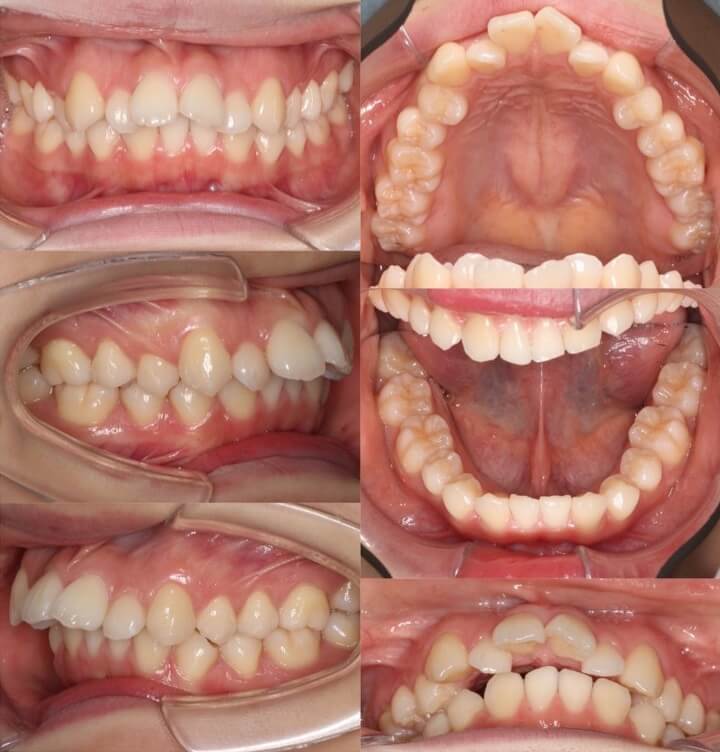

20代女性・先天性欠損2歯・下5欠損

前歯を後ろに倒し込まないように注意しながら、顎間ゴムを使って下の奥歯を前方移動して下の欠損スペースを閉鎖しました。上の抜歯部位は、左右の非対称にすることでうまく正中線を合わせました。下5番抜歯空隙の閉鎖は、後ろにある6番の歯根の移動量が多く治療期間が長くなりやすいです。

<症例概要> 難易度★★★★☆

主訴:下の欠損歯の空隙

年齢・性別:20代女性

症状:左右下5番欠損・空隙・右7シザーズバイト・下顎左偏

治療方針:上顎歯列拡大・下顎臼歯近心移動・

抜歯:右上5番・左上4番

固定装置:アーム付きリンガルアーチ・圧下アーチ・II級ゴム

治療装置:唇側矯正装置

治療期間:2年10か月

リテーナー:上下プレートタイプ

治療費用:990,000(税込)

代表的副作用:痛み・治療後の後戻り・歯根吸収・歯髄壊死・歯肉退縮